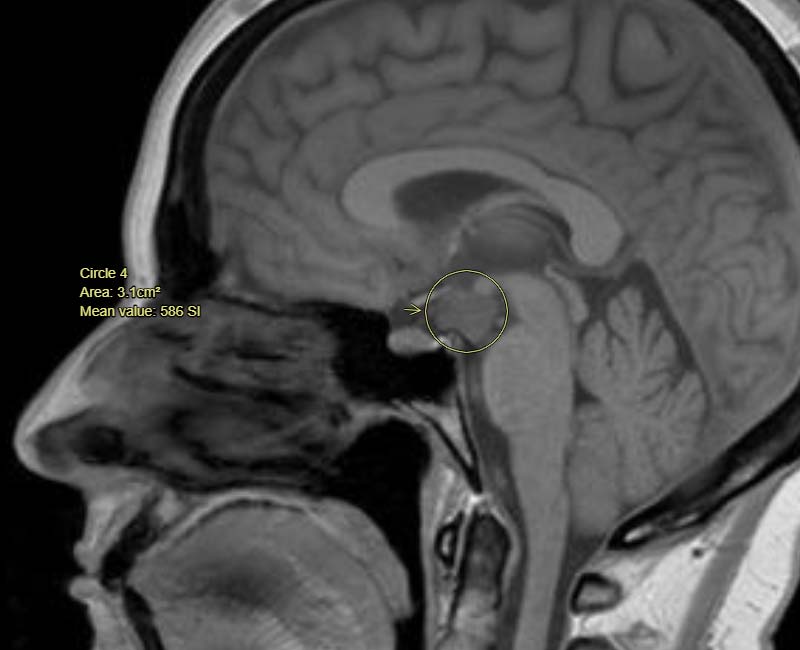

Hypothalamic hamartoma

Tumors of the hypothalamus

Associated with aggression, rage attacks, reduced threshold for frustration, and extensive reactivity to minor stimuli